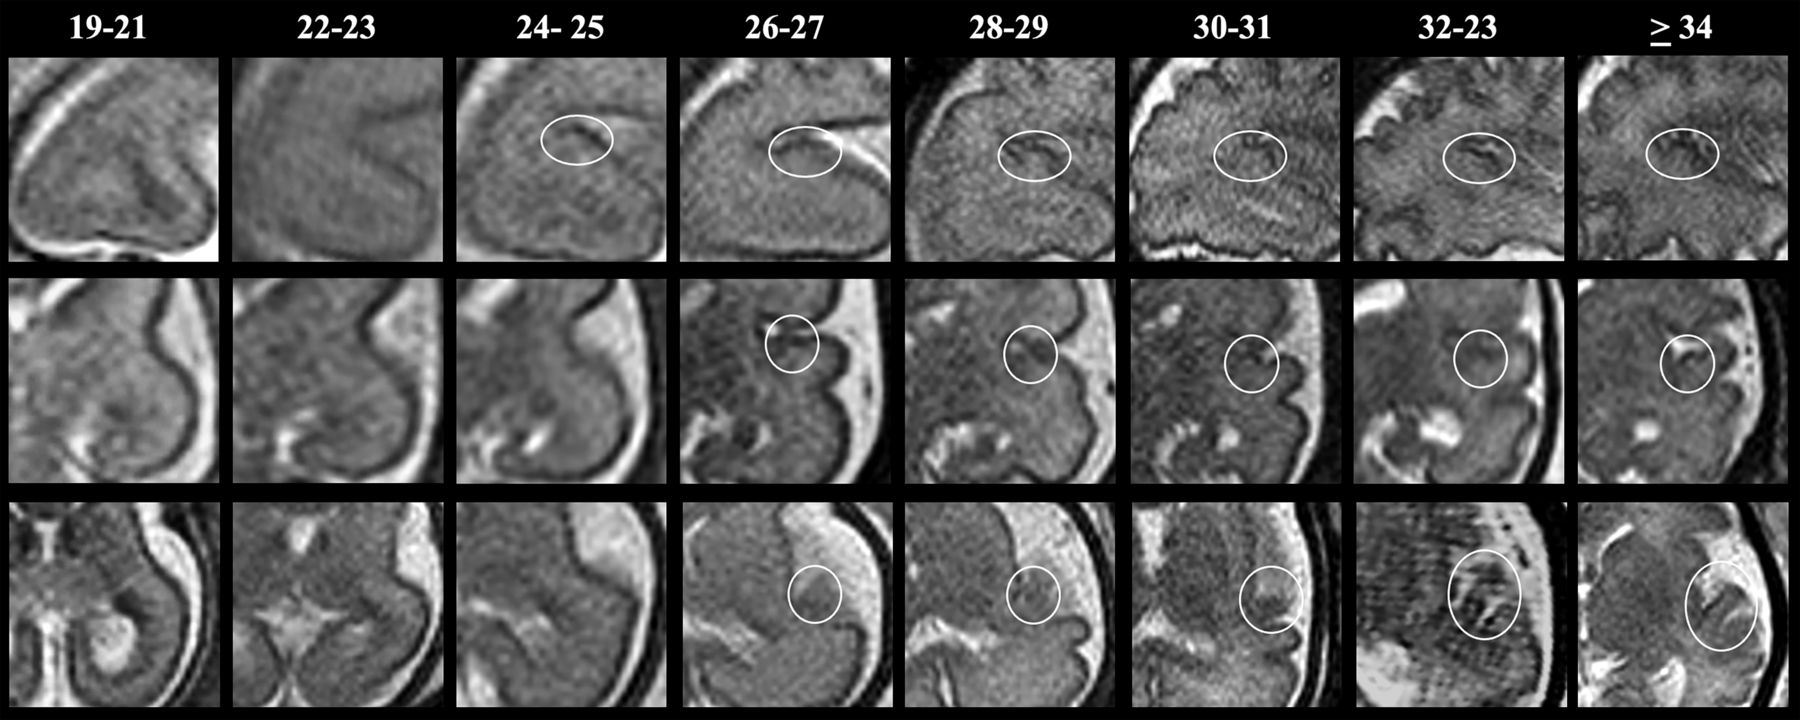

The HG becomes detectable in the earliest gestational weeks of the sagittal plane (24–25 weeks). The structure emerges as a little hump on the posterior part of the superior temporal gyrus. It then reaches a mushroom-like shape abutting the Sylvian fissure from 28 to 29 weeks' GA and further beyond.

SSh T2WI sagittal (upper row), coronal (middle row), and axial (lower row) MR images illustrating changes in HG morphology with increasing GA.

On the coronal sections, the HG begins to be visible from 26 to 27 weeks' GA in the upper and most medial part of the superior temporal gyrus. In these earliest stages, the HG emerges as a little point. With GA progression, the HG becomes an evident protrusion, and from the 34 weeks' GA onward, it appears as a hill-shaped structure.

On axial sections, the HG begins to be visible around 26 weeks' GA, when it emerges as a blurred oblique gyrus with a posterior-anterior and medial-lateral course, deep in the lateral fissure. The HG becomes more defined in the intermediate stages of gestation (28–29 and 30–31 weeks) and reaches a thin, undulated gyral morphology at the edges of the Sylvian fissure in more advanced GA stages (>32 weeks).

By 28–29 weeks' GA, the HG becomes visible in all fetuses and planes (Table and Figs 5 and 6).